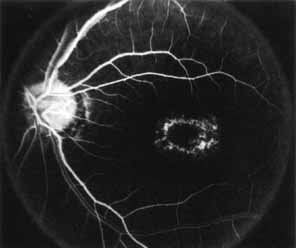

Fluorescein angiography demonstrates increased transmission of choroidal fluorescence in the macula during early phases of the study, without late leakage of dye or fluorescein staining. In addition, an annular pattern of hyperfluorescence is often seen in the macula, highlighting the bull's-eye pattern seen on fundus examination (Fig. 4). Visual field defects include central scotoma, peripheral field loss, and ring scotoma.